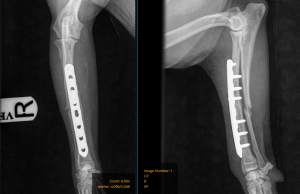

At her five-week post-operative check, Jill was doing really well. She was walking without lameness, and follow-up radiographs showed good progression of bone healing.

Five-week post-op X-rays